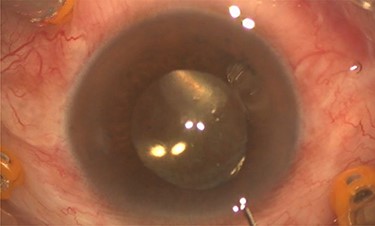

Pars plana vitrectomy and posterior capsulotomy were done. After placing three 23-gauge trocars, a corneal paracentesis was made. After IOL tapping, the entrapped turbid fluid escaped to the anterior chamber (Fig. 3). Anterior vitrectomy and posterior capsulotomy were done using a 23-gauge vitrector (Fig. 4).

Intra-operative photo showed the posterior capsulotomy using 23G vitrector.